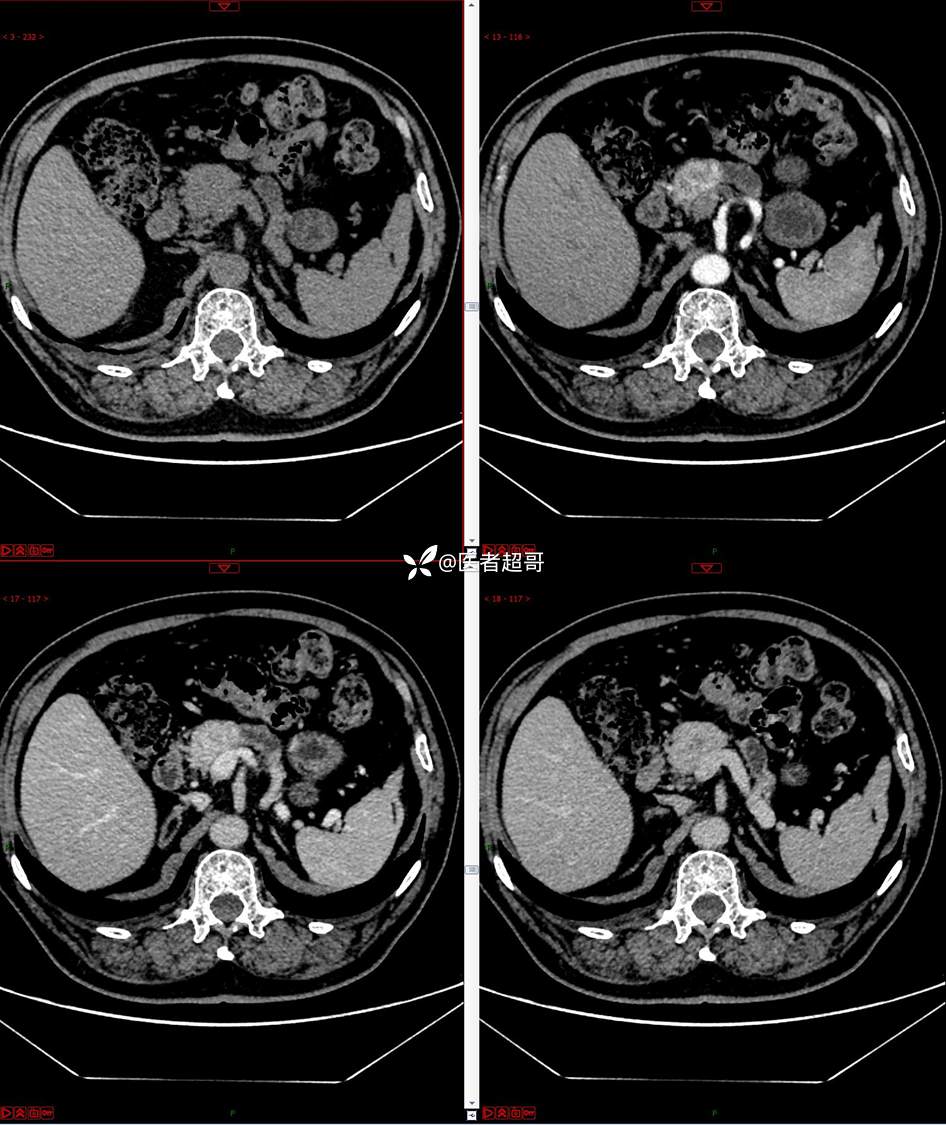

【影诊笔记677】查体发现胰腺占位性病变1周,细节决定成败,请诊断分析!

主 诉:查体发现胰腺占位性病变1周。

现病史:患者1周前在当地查体时发现胰腺占位性病变,无恶心、呕吐,无腹痛,无寒战、高热,无咳嗽、咳痰等异常不适,来我院门诊查上腹部CT平扫+强化:胰腺尾部异常密度灶。今为求进一步治疗,门诊以“胰腺占位性病变”收入院。患者自发病以来,一般情况可,神志清,精神可,普通饮食,二便正常,体重及体力无明显改变。

既往史:既往糖尿病病史2年,口服二甲双胍早晚各一片和格列吡嗪早晚各一片,否认高血压、心脑血管病等疾病史,否认肝炎、结核或其他传染病史及密切接触史,预防接种史不详,否认药物及食物过敏史,否认外伤史,12年前肾癌切除术手术史,否认输血史,其它无特殊。